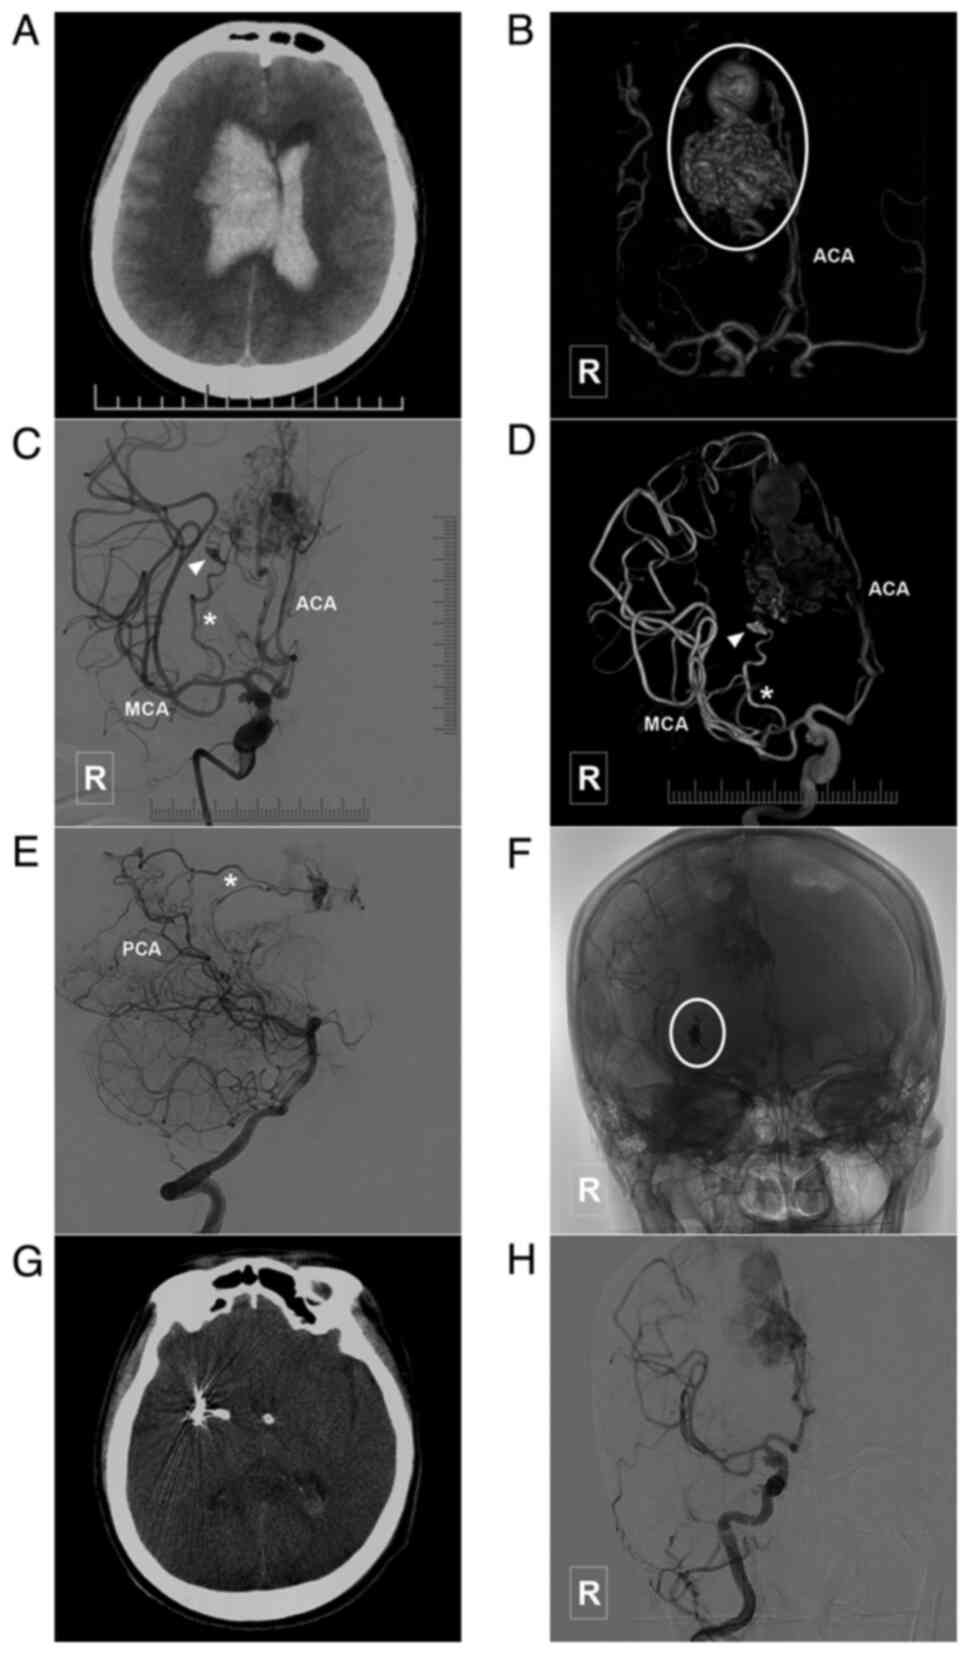

Figure 3

Typical case of a type I ACA-BAVM with flow-related aneurysm. (A) Head CT scan illustrating a subarachnoid hemorrhage in the interhemispheric fissure with hydrocephalus. (B) Head CTA scan illustrating an aneurysm (arrow) located in a branch of the ACA. (C) Angiogram of the right internal carotid artery in lateral view indicates a flow-related aneurysm (arrow) in the feeding artery of an ACA-BAVM. The BAVM is supplied by multiple branches (asterisk) of the ACA. (D) X-ray of the cranium indicating Onyx casting (encircled area) following embolization. (E) Angiogram of the right internal carotid artery after embolization illustrating that the aneurysm in the feeding artery is embolized. There is some remnant of the BAVM (encircle area) and some feeding arteries (asterisk). (F) Post-treatment CT scan illustrating that the patient undergoes external ventricular drainage. ACA, anterior cerebral artery; BAVM, brain arteriovenous malformation; CT, computed tomography; CTA, computed tomography angiography; R, right.

Figure 4

Typical case of a type II BAVM with flow-related aneurysm in the ACA branch. (A) Head CT scan illustrating a hemorrhage in the right frontal lobe. (B) Head CTA scan illustrating a BAVM supplied by the branch of the ACA (encircled area). (C and D) Angiogram of the right internal carotid artery in (C) lateral view and (D) three-dimensional angiogram of the right internal carotid artery indicating that the BAVM is supplied by a single branch of the ACA, with a dissecting aneurysm (arrow) at the beginning of supplying artery. (E) X-ray of the cranium illustrating Onyx casting (encircled area). (F) Angiogram of the right internal carotid artery following treatment indicating the complete embolization of the BAVM and flow-related aneurysm. ACA, anterior cerebral artery; BAVM, brain arteriovenous malformation; CT, computed tomography; CTA, computed tomography angiography; R, right.

Figure 5

Typical case of a type II BAVM with multiple flow-related aneurysms in the ACA trunk. (A) Head CT scan illustrating a hemorrhage in the interhemispheric fissure. (B) Head CTA illustrating a BAVM (encircled area) supplied by the ACA trunk with multiple flow-related aneurysms (arrows). (C) Angiogram of the left internal carotid artery illustrating that the BAVM is supplied by the ACA trunk with two flow-related aneurysms (arrows). (D) Angiogram of the left internal carotid artery following embolization illustrating that the aneurysms are occluded with coils. ACA, anterior cerebral artery; BAVM, brain arteriovenous malformation; CT, computed tomography; CTA, computed tomography angiography; L, left.

Figure 6

Typical case of a type III BAVM. (A) Head CT scan illustrating a hematoma located in the right fronto-parietal lobe. (B) Head CTA illustrating a BAVM (encircled area) supplied the A4-A5 segment of ACA and drained to the sagittal sinus. (C) Angiogram of the left vertebral artery illustrating that the posterior circulation is not involved in the blood supply of the BAVM. (D) Three-dimensional angiogram of the right internal carotid artery illustrating that the terminal branch of the ACA is involved in the blood supply of the BAVM. (E) X-ray of the cranium illustrating Onyx casting. The arrow denotes the coils in the feeding artery near the nidus, and the ‘pressure cooker’ technique (before Onyx casting, the coiling was performed to occlude the feeding artery to prevent Onyx reflux) is used during treatment. (F) Angiogram of the right internal carotid artery following treatment illustrating that the BAVM is almost completely embolized, while the draining veins (encircled area) remains. ACA, anterior cerebral artery; BAVM, brain arteriovenous malformation; CT, computed tomography; CTA, computed tomography angiography; L, left; R, right.

Figure 7

Typical case of a type III BAVM with multiple flow-related aneurysms in the ACA trunk. (A) Head CT scam illustrating a subarachnoid hemorrhage in the interhemispheric fissure. (B) Head CTA illustrating a BAVM (encircled area) supplied the ACA, MCA and PCA, and which drained to the sagittal sinus. The ACA is the main feeding artery, with multiple flow-related aneurysms (arrow and arrow head). (C) Angiogram of the left vertebral artery shows that the posterior circulation is involved in the blood supply of the BAVM. (D) A stent was used to assist in coiling of the aneurysm (arrow) in the ACA. (E) MRI at 3 days post-treatment reveals a new hemorrhage in the interhemispheric fissure, which is considered to be caused by re-rupture of the aneurysm. (F and G) Parent artery occlusion is performed to occlude the aneurysm and the parent artery (arrow). (H) Angiogram of the right internal carotid artery in venous phase illustrating retrograde blood supply from the BAVM to the frontal lobe (encircled area) through the ACA (asterisk). ACA, anterior cerebral artery; BAVM, brain arteriovenous malformation; CT, computed tomography; CTA, computed tomography angiography; L, left; MCA, middle cerebral artery; MRI, magnetic resonance imaging; PCA, posterior cerebral artery; R, right.